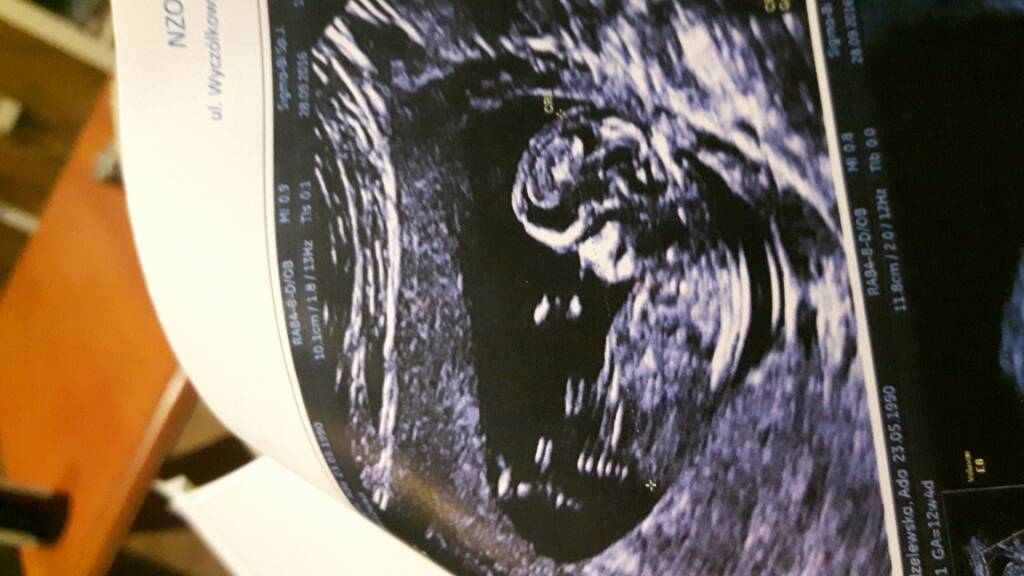

Nasza testy, usg, wizyty :-)

Cud nad cudy [emoji4][emoji4][emoji4]

Piekne Dziudziusie !!!